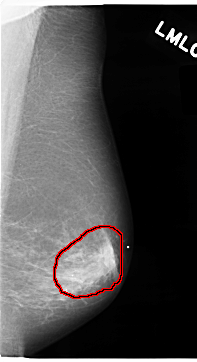

C_0074_1.RIGHT_MLO

FILE: C_0074_1.LEFT_MLO.OVERLAY

TOTAL_ABNORMALITIES 1

ABNORMALITY 1

LESION_TYPE MASS SHAPE IRREGULAR MARGINS SPICULATED

ASSESSMENT 5

SUBTLETY 5

PATHOLOGY MALIGNANT

TOTAL_OUTLINES 1

BOUNDARY